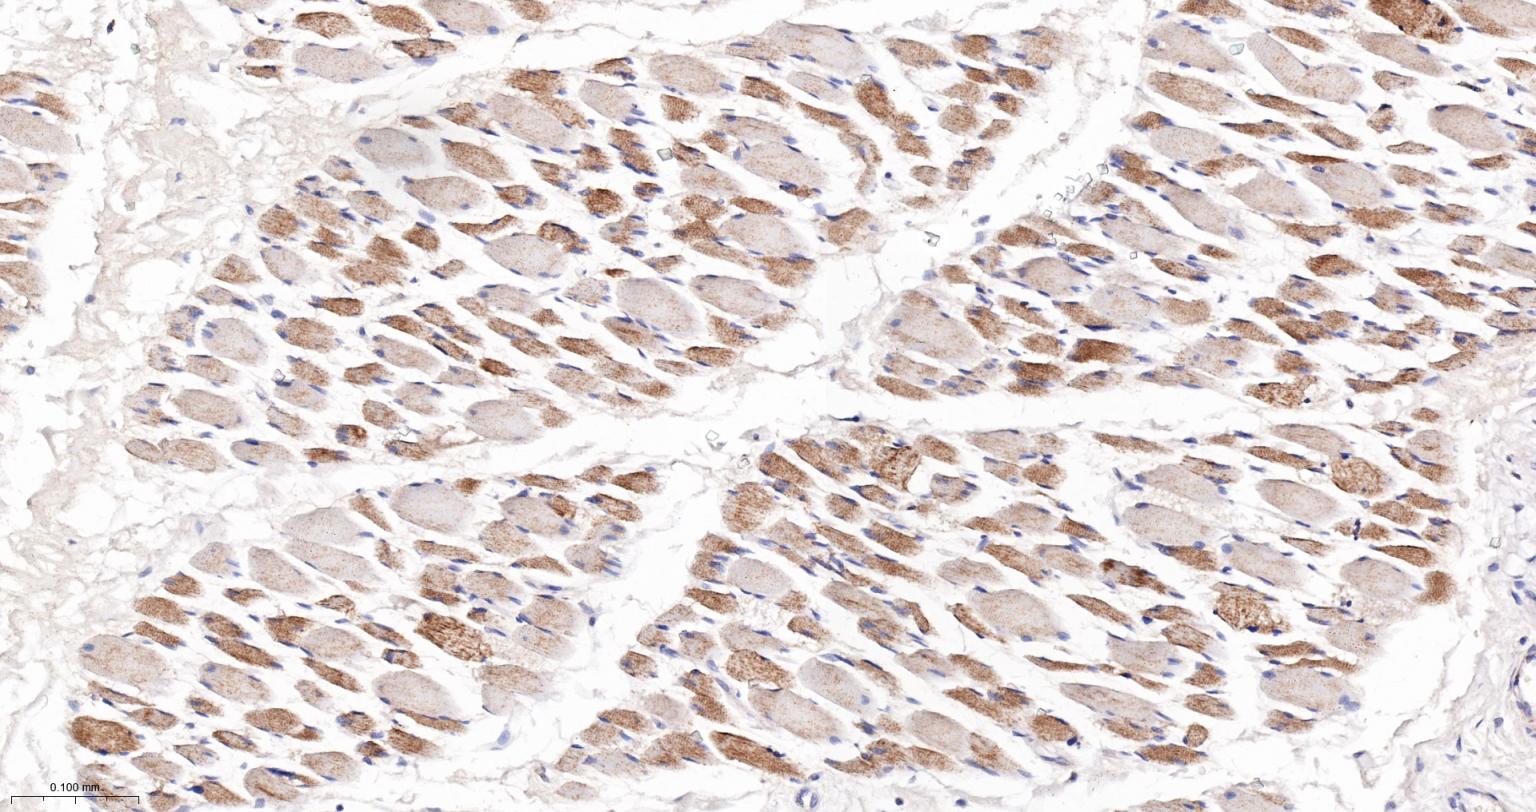

Paraformaldehyde-fixed, paraffin embedded Human Heart; Antigen retrieval by boiling in sodium citrate buffer (pH6.0) for 15 min; The section was incubated with ATP5MC1 Monoclonal Antibody, Unconjugated (bsm-61256R) at 1:200 overnight at 4°C, followed by conjugation to the bs-0295G-HRP and DAB (C-0010) staining.